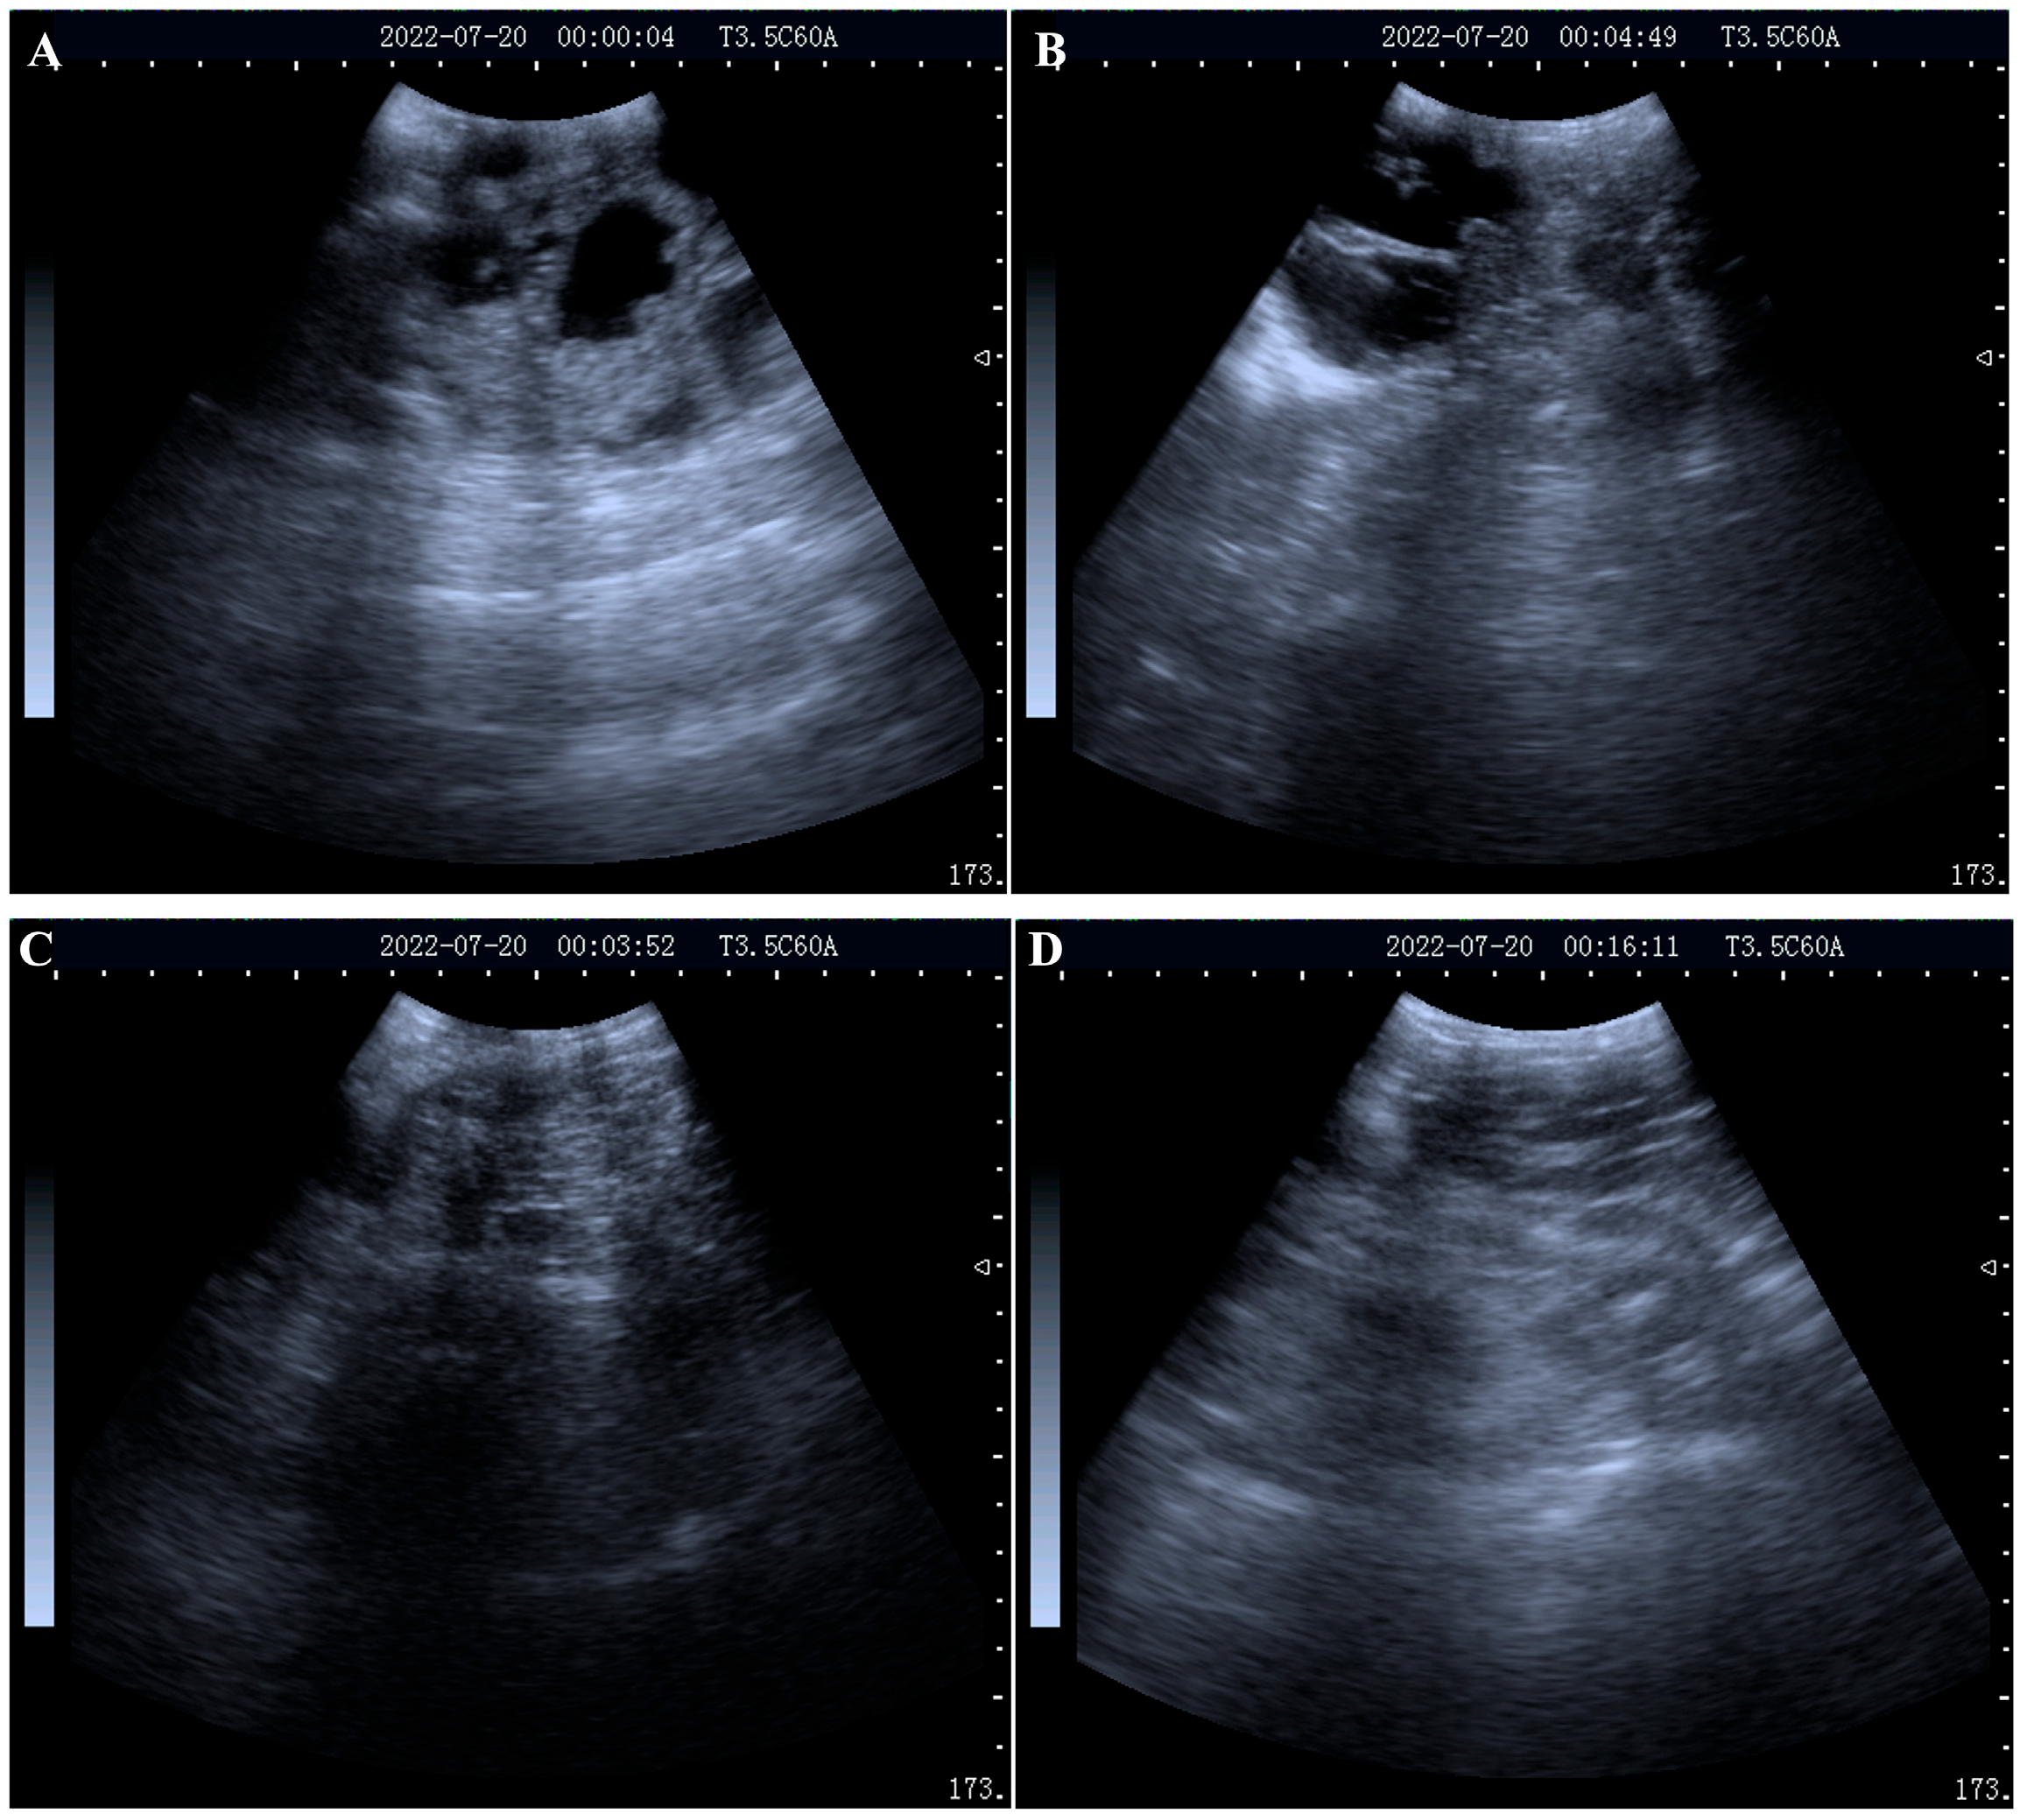

2.1. Serum Collection and Pregnancy Diagnosis